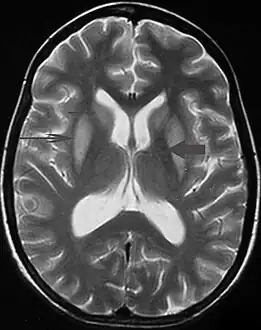

In about ten per cent of people with central pontine myelinolysis, extrapontine myelinolysis is also found. In these cases symptoms of Parkinson's disease may be generated.[7]

It can be diagnosed clinically in the appropriate context, but may be difficult to confirm radiologically using conventional imaging techniques. Changes are more prominent on MRI than on CT, but often take days or weeks after acute symptom onset to develop. Imaging by MRI typically demonstrates areas of hyperintensity on T2-weighted images.[27]